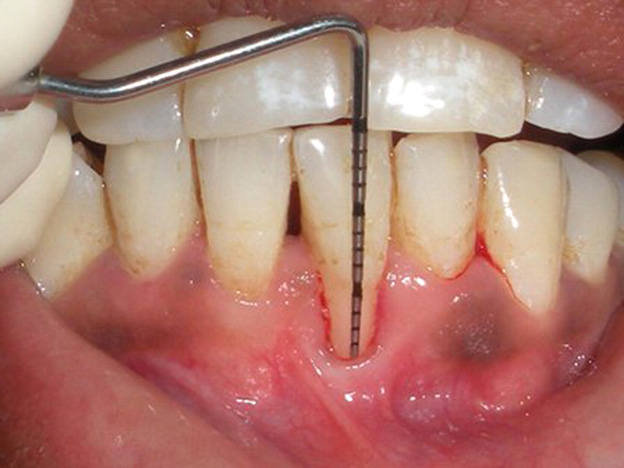

Diagnosis

A routine dental examination can identify and uncover gum recession. The dentists will utilize a specialized instrument known as a periodontal probe to measure and assess the depth of periodontal pockets surrounding each tooth. Individuals with healthy gum have these pockets measured between 1 and 3 millimeters. Those with gingivitis may have these pockets at around 4 millimeters. However, those with periodontal disease may have pockets deeper than 5 millimeters. People with gum recession usually have accompanied bone loss.